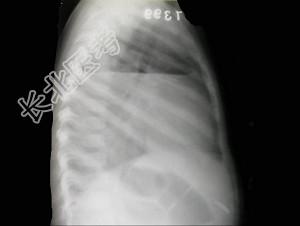

- 单项选择题男,7岁, 外伤后突发呼吸困难伴胸痛,结合图像, 最可能的诊断是 ( )

A、胸腔积液

B、肺大泡

C、气胸

D、液气胸

E、肺脓肿